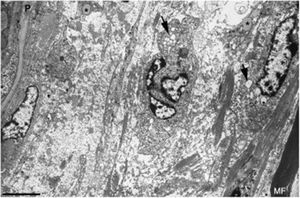

Imagen ultraestructual de la región superineural de la figura 2E. Hay un marcado edema endoneural con material amorfo, probablemente proteoglicano, y haces dispersos de fibrillas de colágeno. Nótese la presencia de macrófagos que contienen gotas lipídicas (asteriscos), así como numerosas vesículas de endocitosis (flechas) y lisosomas. En el área edematosa no hay fibras mielinizadas; la única observada (MF) se sitúa a 20μm del perineuro (P) (barra, 3μm).